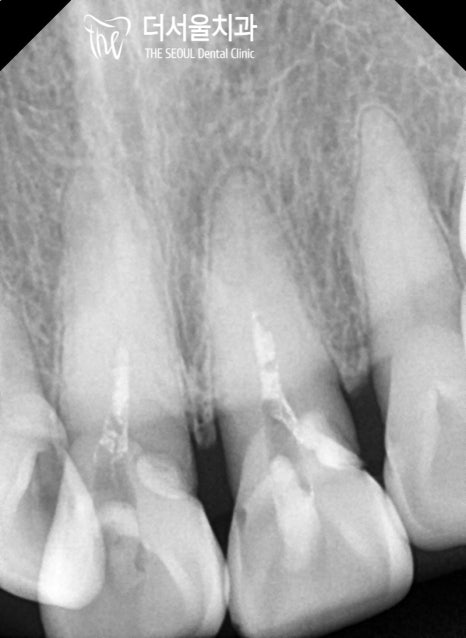

초진 구강 사진을 보면

곳곳에 생긴 우식과 치경부 마모증이

나타나 있는 것을 볼 수 있는데요.

눈에 잘 띄지 않는 곳까지 꼼꼼하게

살펴보는 것이 중요하기 때문에

치근단 방사선을 촬영하여 살펴본 결과

노인에게서 잘 발생하는 치근우식이

나타나 있는 것으로 확인되었습니다.

앞니 주변으로 치근 우식이 생긴 것으로 판단되어

# 11 # 21 엔도 코어 크라운,

# 12 레진 치료